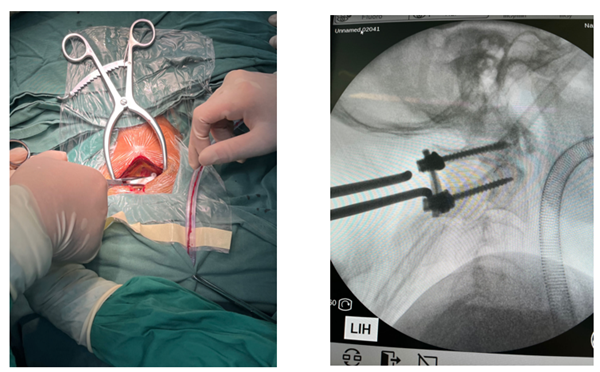

A subtype of powder bed fusion, LPBF uses a metal powder bed and one or more (up to 12) high-power lasers. LPBF 3D printers use lasers to selectively fuse metal powders layer by layer on a molecular basis until the pattern is complete. LPBF is a high-precision 3D printing method commonly used to create complex metal parts for aerospace, medical and industrial applications.